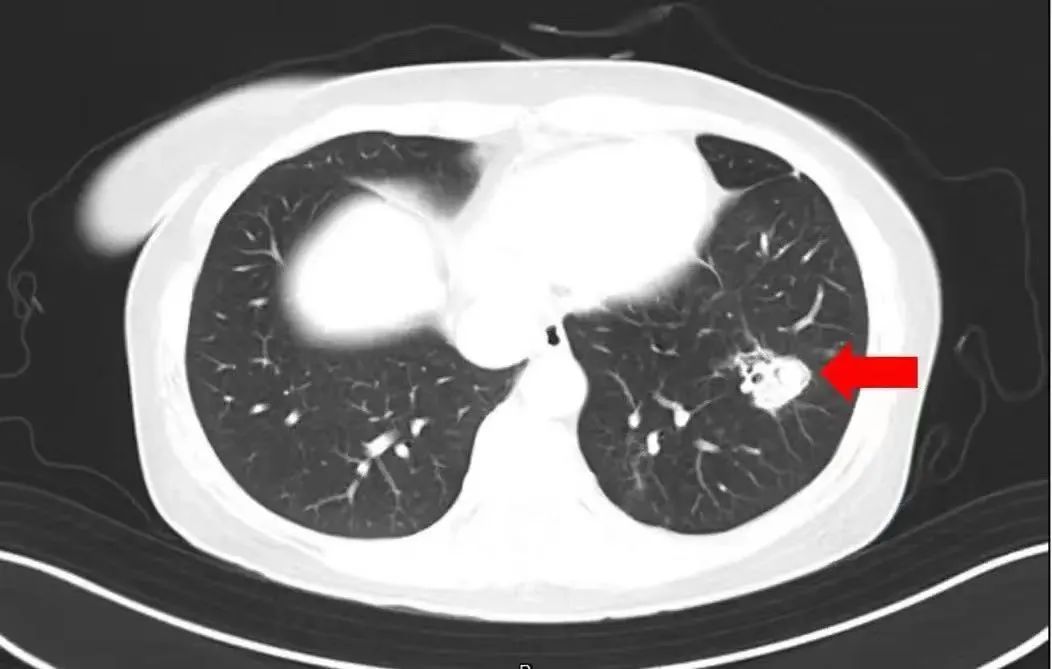

在了解情况后,医生为她做了纤维支气管镜检查及肺泡灌洗液病原体检测,果然发现气道壁上有大量白色菌斑,这就是引起患者高烧、咳嗽的“元凶”——肺曲霉菌病。

肺曲霉菌病在临床上分为侵入性肺曲霉菌病、肺曲霉球、气管支气管曲霉病等类型。不同类型的肺曲霉菌病临床表现有所不同。

常见的症状有持续高热不退,服用常规退烧药也难以起到明显效果;咳嗽症状不断加重,还可能伴有胸痛、呼吸困难;咳出的痰液中带有血丝或呈现棕褐色;此外,还可能出现鼻塞、流脓涕、面部疼痛等鼻窦炎症状。严重时可发生呼吸衰竭甚至危及生命。